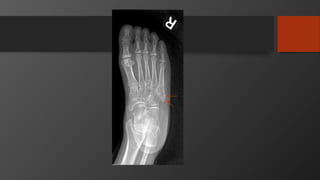

Fifth Metatarsal Fractures

• Common injury

• Divided into 3 zones

• Zone 2 is Jones fracture

• Zone 1 is Pseudojones fracture